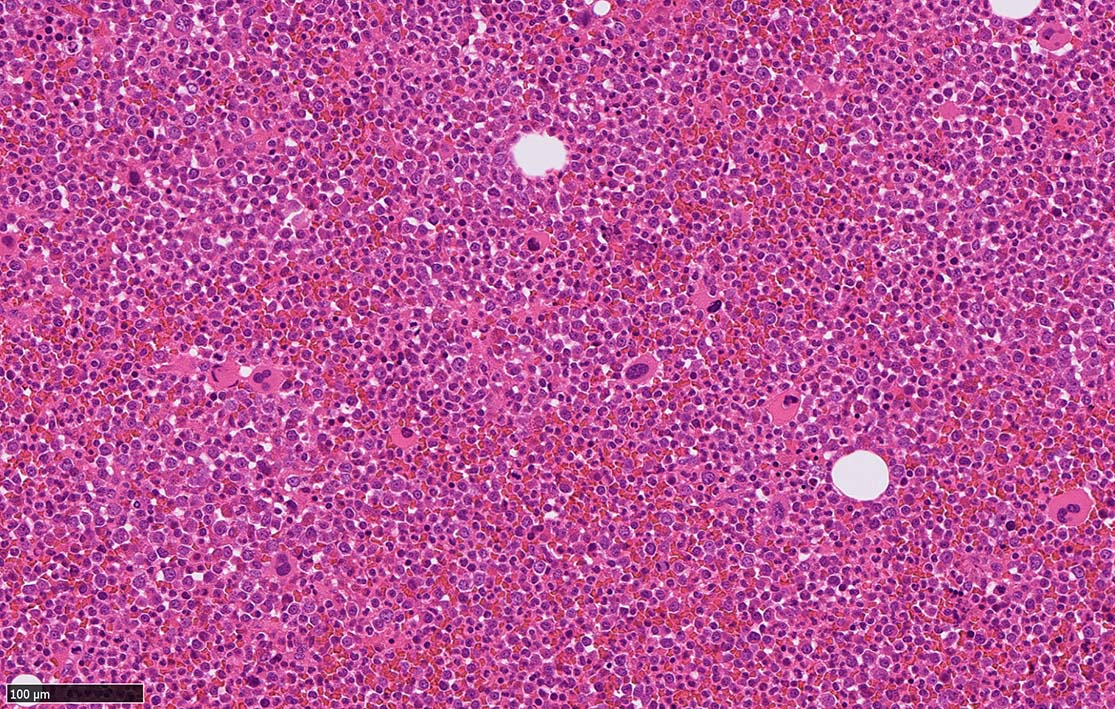

dwarf Mgks 画像を追加する 典型的なCML(chronic phase)の骨髄組織では, 赤芽球血島形成は消失する. 一方 Mgkの数は保たれるが, 「dwarf Mgk」と呼ばれる小型の巨核球が増加する. bizzarreな核をもつMgkも出現する.

典型的なCML(chronic phase)の骨髄組織では, 赤芽球血島形成は消失する. 一方 Mgkの数は保たれるが, 「dwarf Mgk」と呼ばれる小型の巨核球が増加する. bizzarreな核をもつMgkも出現する.